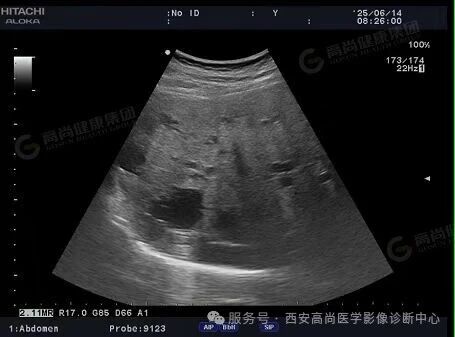

02超声图

03超声所见

肝脏声像图所见:考虑多囊肝;

双侧肾脏声像图所见:考虑多囊肾。

03、超声表现

肾脏: 双肾弥漫性增大,实质内布满大小不等的无回声区(囊肿),边界清晰,严重时正常肾实质被挤压消失。

肝脏: 肝内可见多个无回声区,分布不均,随病情进展囊肿数量和体积增加,肝脏增大。